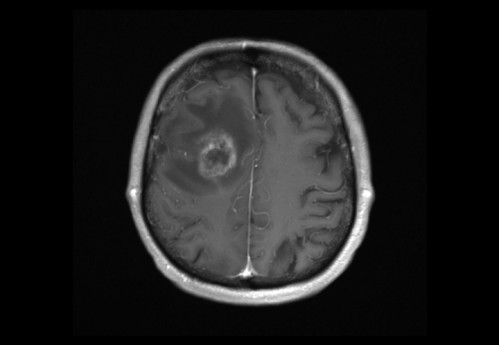

Sie behandeln einen 48-jähriger Mann, von Beruf Architekt. In der Anamnese erfahren Sie, dass er leidenschaftlich Gitarre spiele und er berichtet, dass ihm seit zwei Wochen in der rechten Hand die nötige Koordination fehle. Auch das Plektrum würde ihm immer wieder aus den Fingern gleitet.

Eine Magnet-Resonanz-Tomografie (MRT) des Kopfes wurde durch den ambulant behandelnden Neurologen bereits veranlasst.